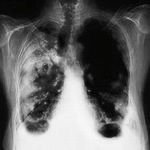

К сожалению, в большинстве случаев это заболевание протекает совершенно бессимптомно. Кашель, боли в грудине, мокрота появляются лишь тогда, когда случай уже запущен, то есть в 3-й, 4-й стадии. А в первой стадии этот вид рака выявить, как правило, очень трудно. Это возможно только при периферической опухоли.

Да. Я считаю это достижением советского здравоохранения. В связи с этим и выявляемость рака легкого в бывшем Советском Союзе была одной из самых высоких в мире. Периферическую опухоль легкого при флюорографии можно обнаружить даже на первой стадии (опухоль до 1 см)! И в основном те больные, которые поступают к нам в клинику на ранних стадиях, узнали о своем диагнозе именно после планового прохождения флюорографии. Хотя рак, располагающийся в центре легкого либо в бронхах, к сожалению, выявить с ее помощью гораздо сложнее.